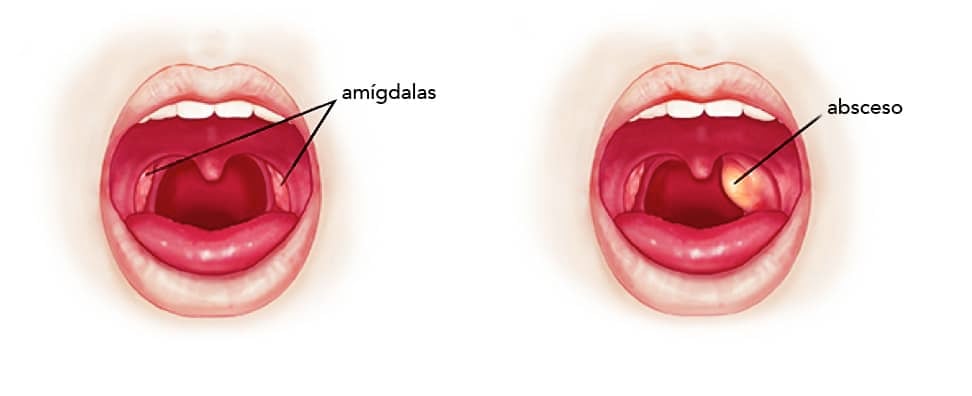

- Tratamiento de amigdalitis y faringitis recurrente

- Cirugías de amígdalas, adenoides y tabique nasal

No, los otorrinolaringólogos también atienden a niños con problemas como otitis recurrentes, amigdalitis crónica y dificultades respiratorias.